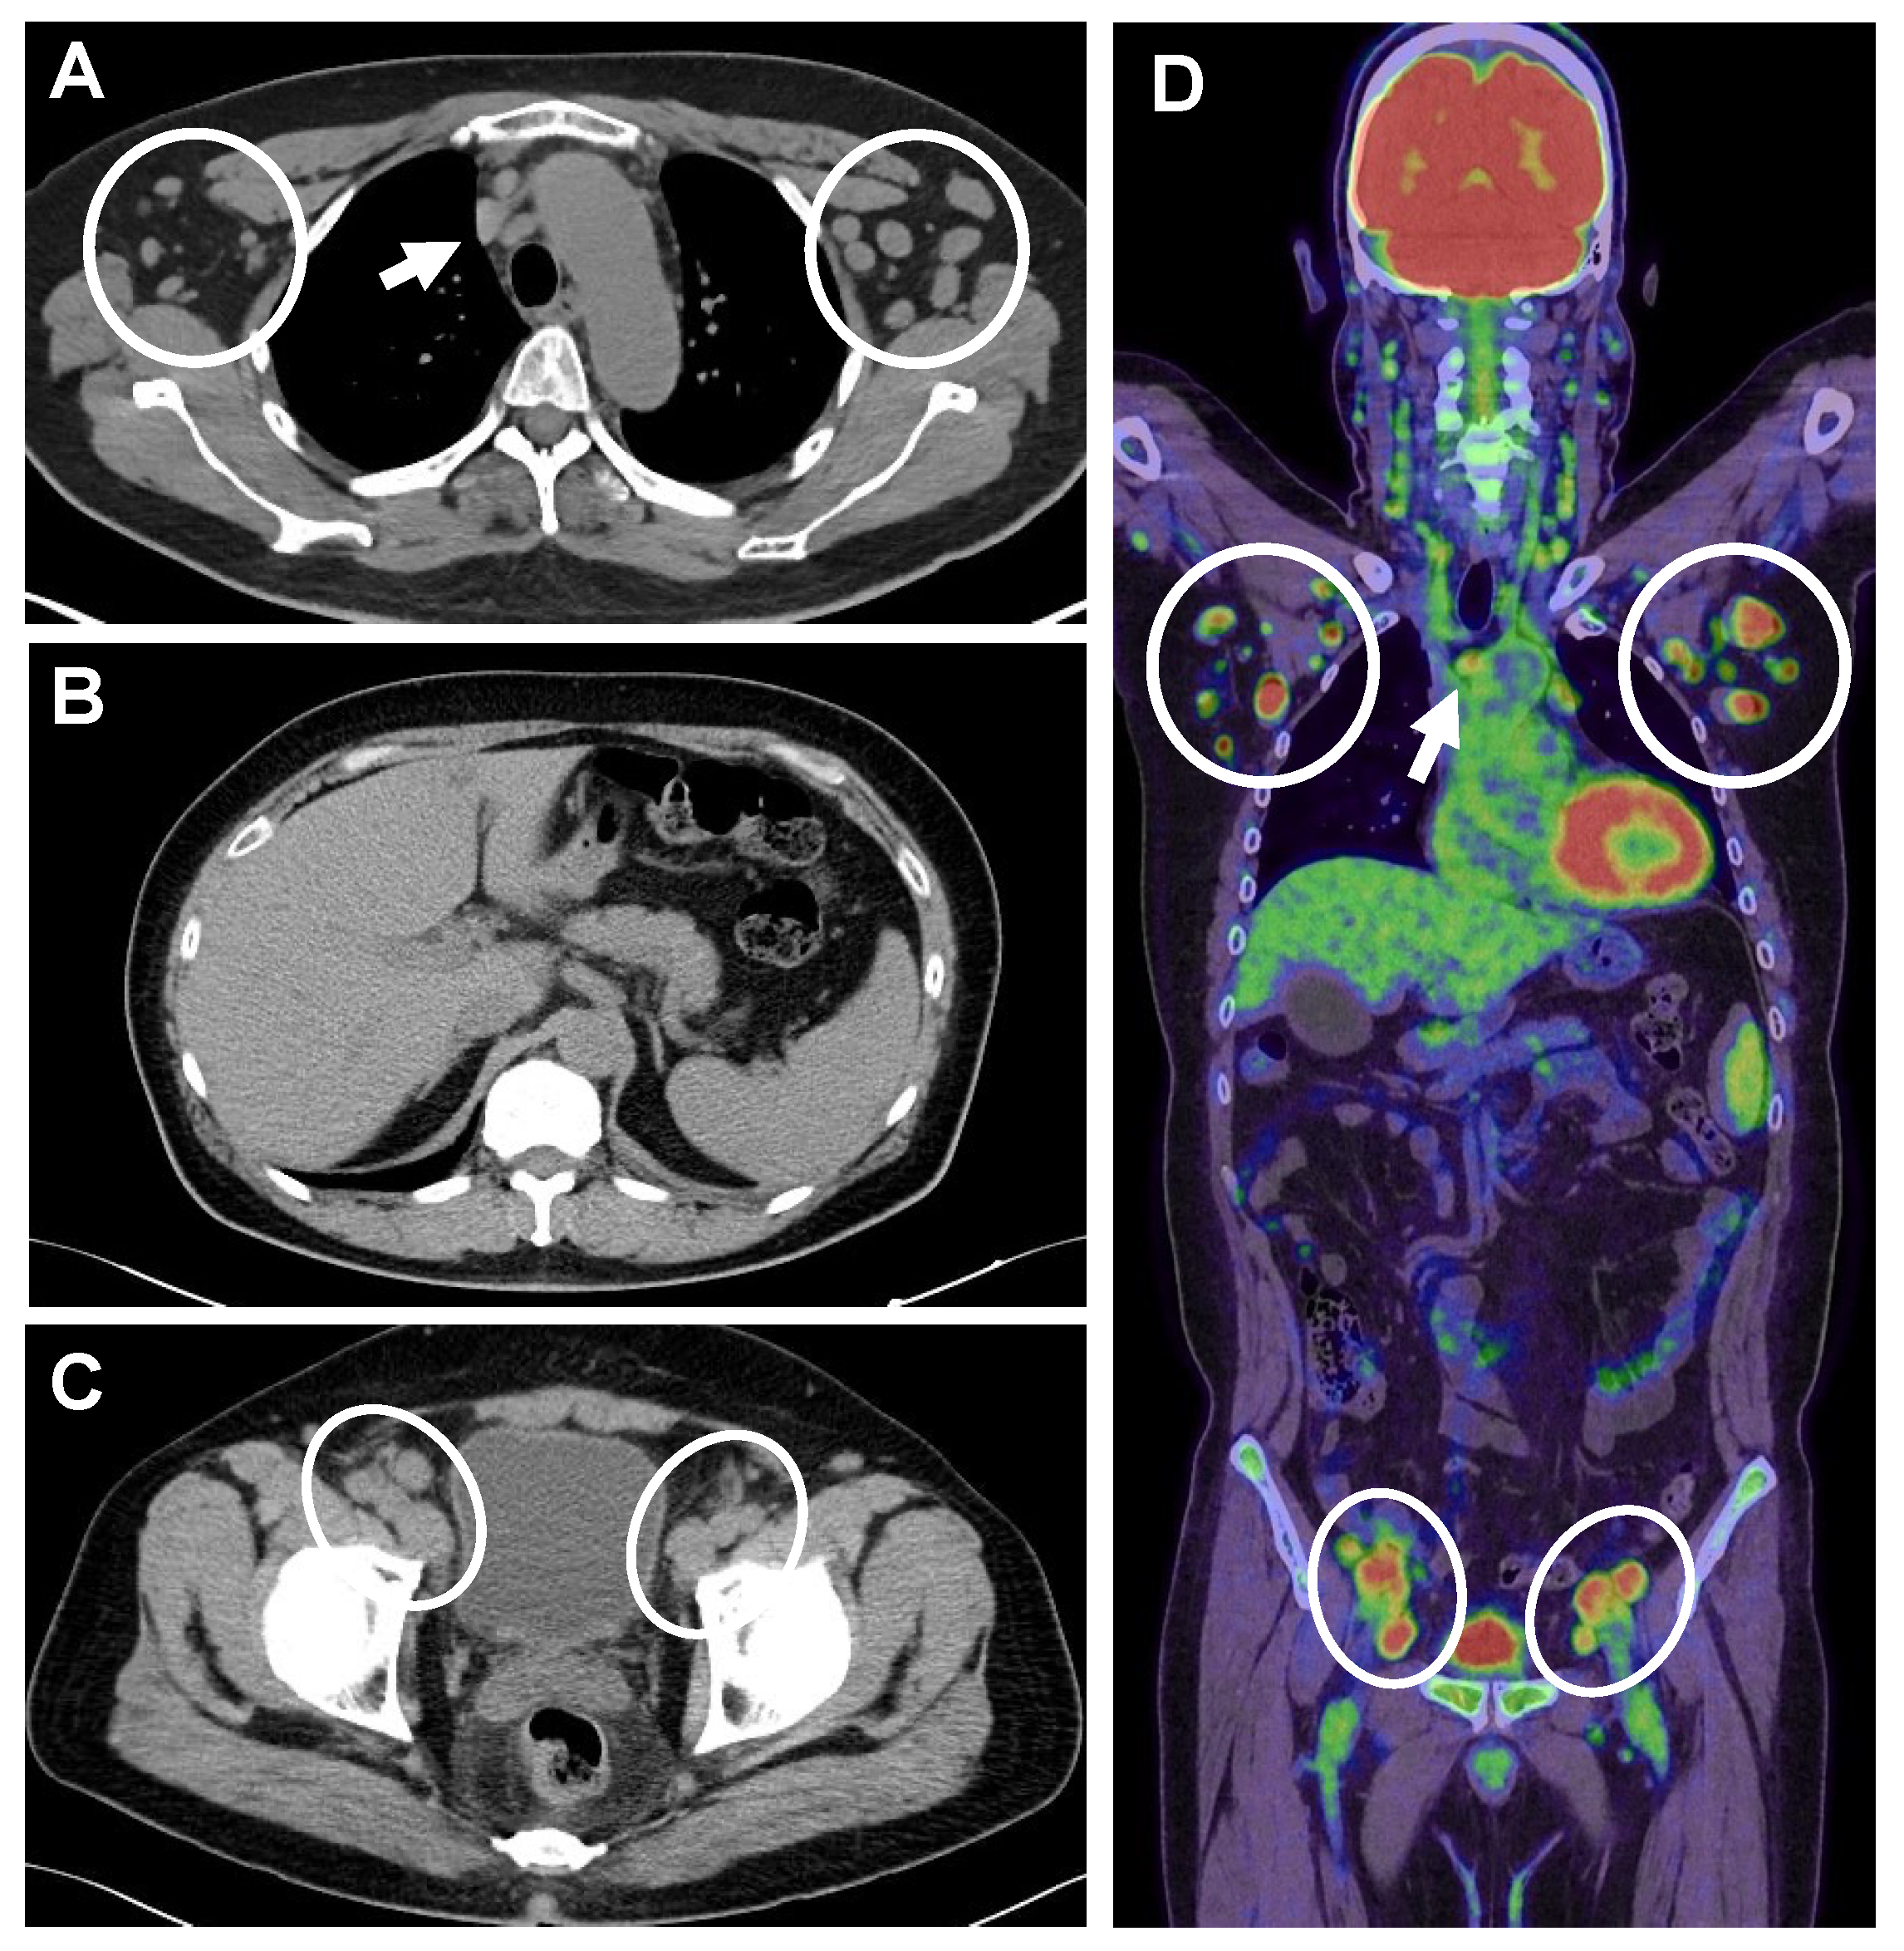

2. Case Presentation